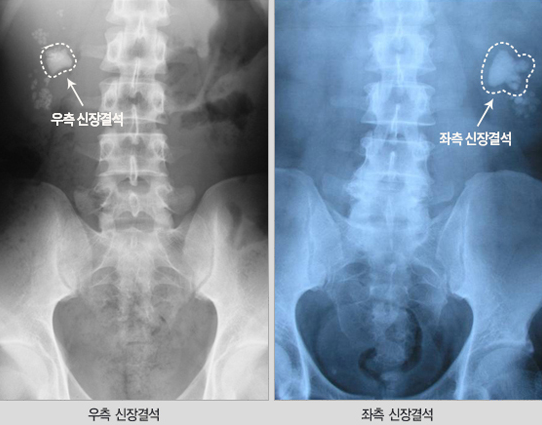

신장 결석은 비뇨의학과, 소아비뇨의학과에서 진료 받을 수 있습니다. 신장 결석이 의심된다면 신장 결석의 가족력, 과거력, 통풍 여부, 환자의 증상을 확인합니다. 이후에 방사선 촬영, CT, 초음파 검사 등으로 결석의 위치와 크기를 확인하고 필요시 혈액 검사, 소변 화학 분석 검사를 시행할 수 있습니다.

- 복부 방사선 촬영, 복부초음파, 복부 컴퓨터단층촬영(CT)등을 통해 신장결석의 위치를 확인 합니다. 필요시 조영제를 이용한 컴퓨터단층촬영(CT)을 시행하여 정확한 결석의 위치와 소변의 흐름을 막는지 여부 확인, 결석과 동반된 비뇨기계 변형을 알아볼 수 있습니다.